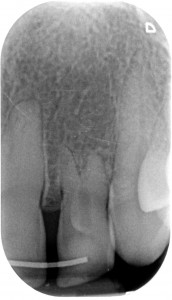

L’anomalia del dentone nella radiografia qui sopra forse è un po’ più facile da riconoscere, ma non sono comunque sicuro che tutti i dentisti sappiano di cosa si tratti e, soprattutto, abbiano idea di che trattamento eseguire.

Il fenomeno rappresentato è chiaramente un Dens Invaginatus, meglio conosciuto come Dens in Dente. In realtà esiste una terza definizione, che è quella della mia assistente Roberta che è portatrice sana di un Dancing Dente ???, che è quello che ha capito lei quando ho emesso la diagnosi guardando la rx del suo incisivo laterale di sinistra! Diagnosi che il suo vecchio dentista non aveva saputo fare…

Con tutta probabilità l’affondamento del dente da latte sulla gemma in formazione del 2.2 ha generato una deformazione dell’organo dello smalto che si è appunto invaginato all’interno della papilla dentale, formando un dens in dente, come dimostra la linea radiopaca che si intravede all’interno del dente, che non è nient’altro che smalto. Uno smalto un po’ meno mineralizzato di quello esterno, se guardiamo alla letteratura, ma pur sempre smalto.

In attesa che anche a te capiti un dens in dente da riconoscere ed eventualmente trattare, ti lascio con il video del dentone che ti ho presentato all’inizio del post. L’ho trattato demolendo il dens in dente e trasformando il canale in un canalone da chiudere con un cemento come l’MTA o la Biodentine. Io preferisco la Biodentine che mi sta dando grandi soddisfazioni e che è più facile da maneggiare, come vedrai nel video! Ne parleremo in un prossimo post, per cui, se non l’hai fatto, iscriviti alla newsletter di Formazione Odontoiatrica! Ne vedremo delle belle!